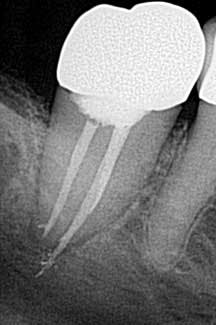

• Missed canals

Know your tooth anatomy and the possible variations of the canals (figure 2). The molars present with the most diverse canal composition—“additional canals in the mesial roots of maxillary molars and the distal roots of mandibular molars are the most frequently missed” (2)—but even the premolars and incisors can prove to be a formidable foe. Remember the article by David Landwehr, DDS, MS, titled “The myth of ‘easy’ root canals in endodontics”? Read it if you haven’t. Lastly, don’t skimp on your occlusal access and use magnification.